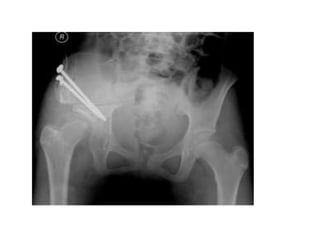

boy aged 9 years 7 months with Group B disease in the lateral pillar classification;

b: femoral varus osteotomy; c: outcome at 11 years of age.

boy aged 9years 7 months with Group B disease in the lateral pillar classification; b: femoral varus osteotomy; c: outcome at 11 years of age.